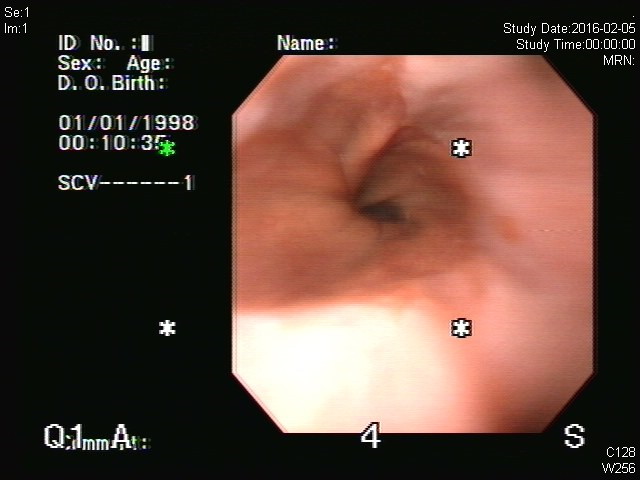

¾Æ·¡ 2013³â ȯÀÚÀÇ ³»½Ã°æ °Ë»çÀÏÀÌ 1998³â 1¿ù 1ÀÏÀÌ°í °Ë»ç ½Ã°£Àº 0½Ã 2ºÐÀ̾ú½À´Ï´Ù. (ÁÂÃø Áß°£). ÀÀ±Þ ȯÀÚµµ ¾Æ´Ñµ¥ 1¿ù 1ÀÏ »õº®ºÎÅÍ °Ë»çÇÏÁö´Â ¾Ê¾Ò°ÚÁö¿ä. ¾îµð°¡ À߸øµÈ °ÍÀϱî¿ä?

°Ë»çÀÏ: 1998³â 1¿ù 1ÀÏ 0½Ã 2ºÐ???

³»½Ã°æ Àåºñ¸¦ ±¸ÀÔÇϸé óÀ½ »ç¿ëÇÒ ¶§ ³¯Â¥¸¦ ¸ÂÃß°Ô µÇ¾î ÀÖ½À´Ï´Ù. À̸¦ ¹«½ÃÇÏ°í ±×³É ³»½Ã°æÀ» »ç¿ëÇϸé '1998/01/01'°ú °°ÀÌ Ç×»ó 1¿ù 1ÀÏ¿¡ °Ë»çÇÑ °ÍÀ¸·Î ³ª¿É´Ï´Ù. Áß°£¿¡ ³»½Ã°æ ½Ã½ºÅÛ ³»Àå ¹èÅ͸®°¡ ¹æÀüµÇ¾î ³¯Â¥°¡ Áö¿öÁø °æ¿ìµµ ºñ½ÁÇÑ Çö»óÀÌ ³ªÅ¸³³´Ï´Ù. °£´ÜÇÑ setting Á¶Á¤À¸·Î ¹Ù·ÎÀâÀ» ¼ö ÀÖ½À´Ï´Ù.

°Ë»çÀÏ: 1998³â 1¿ù 1ÀÏ 0½Ã 10ºÐ???